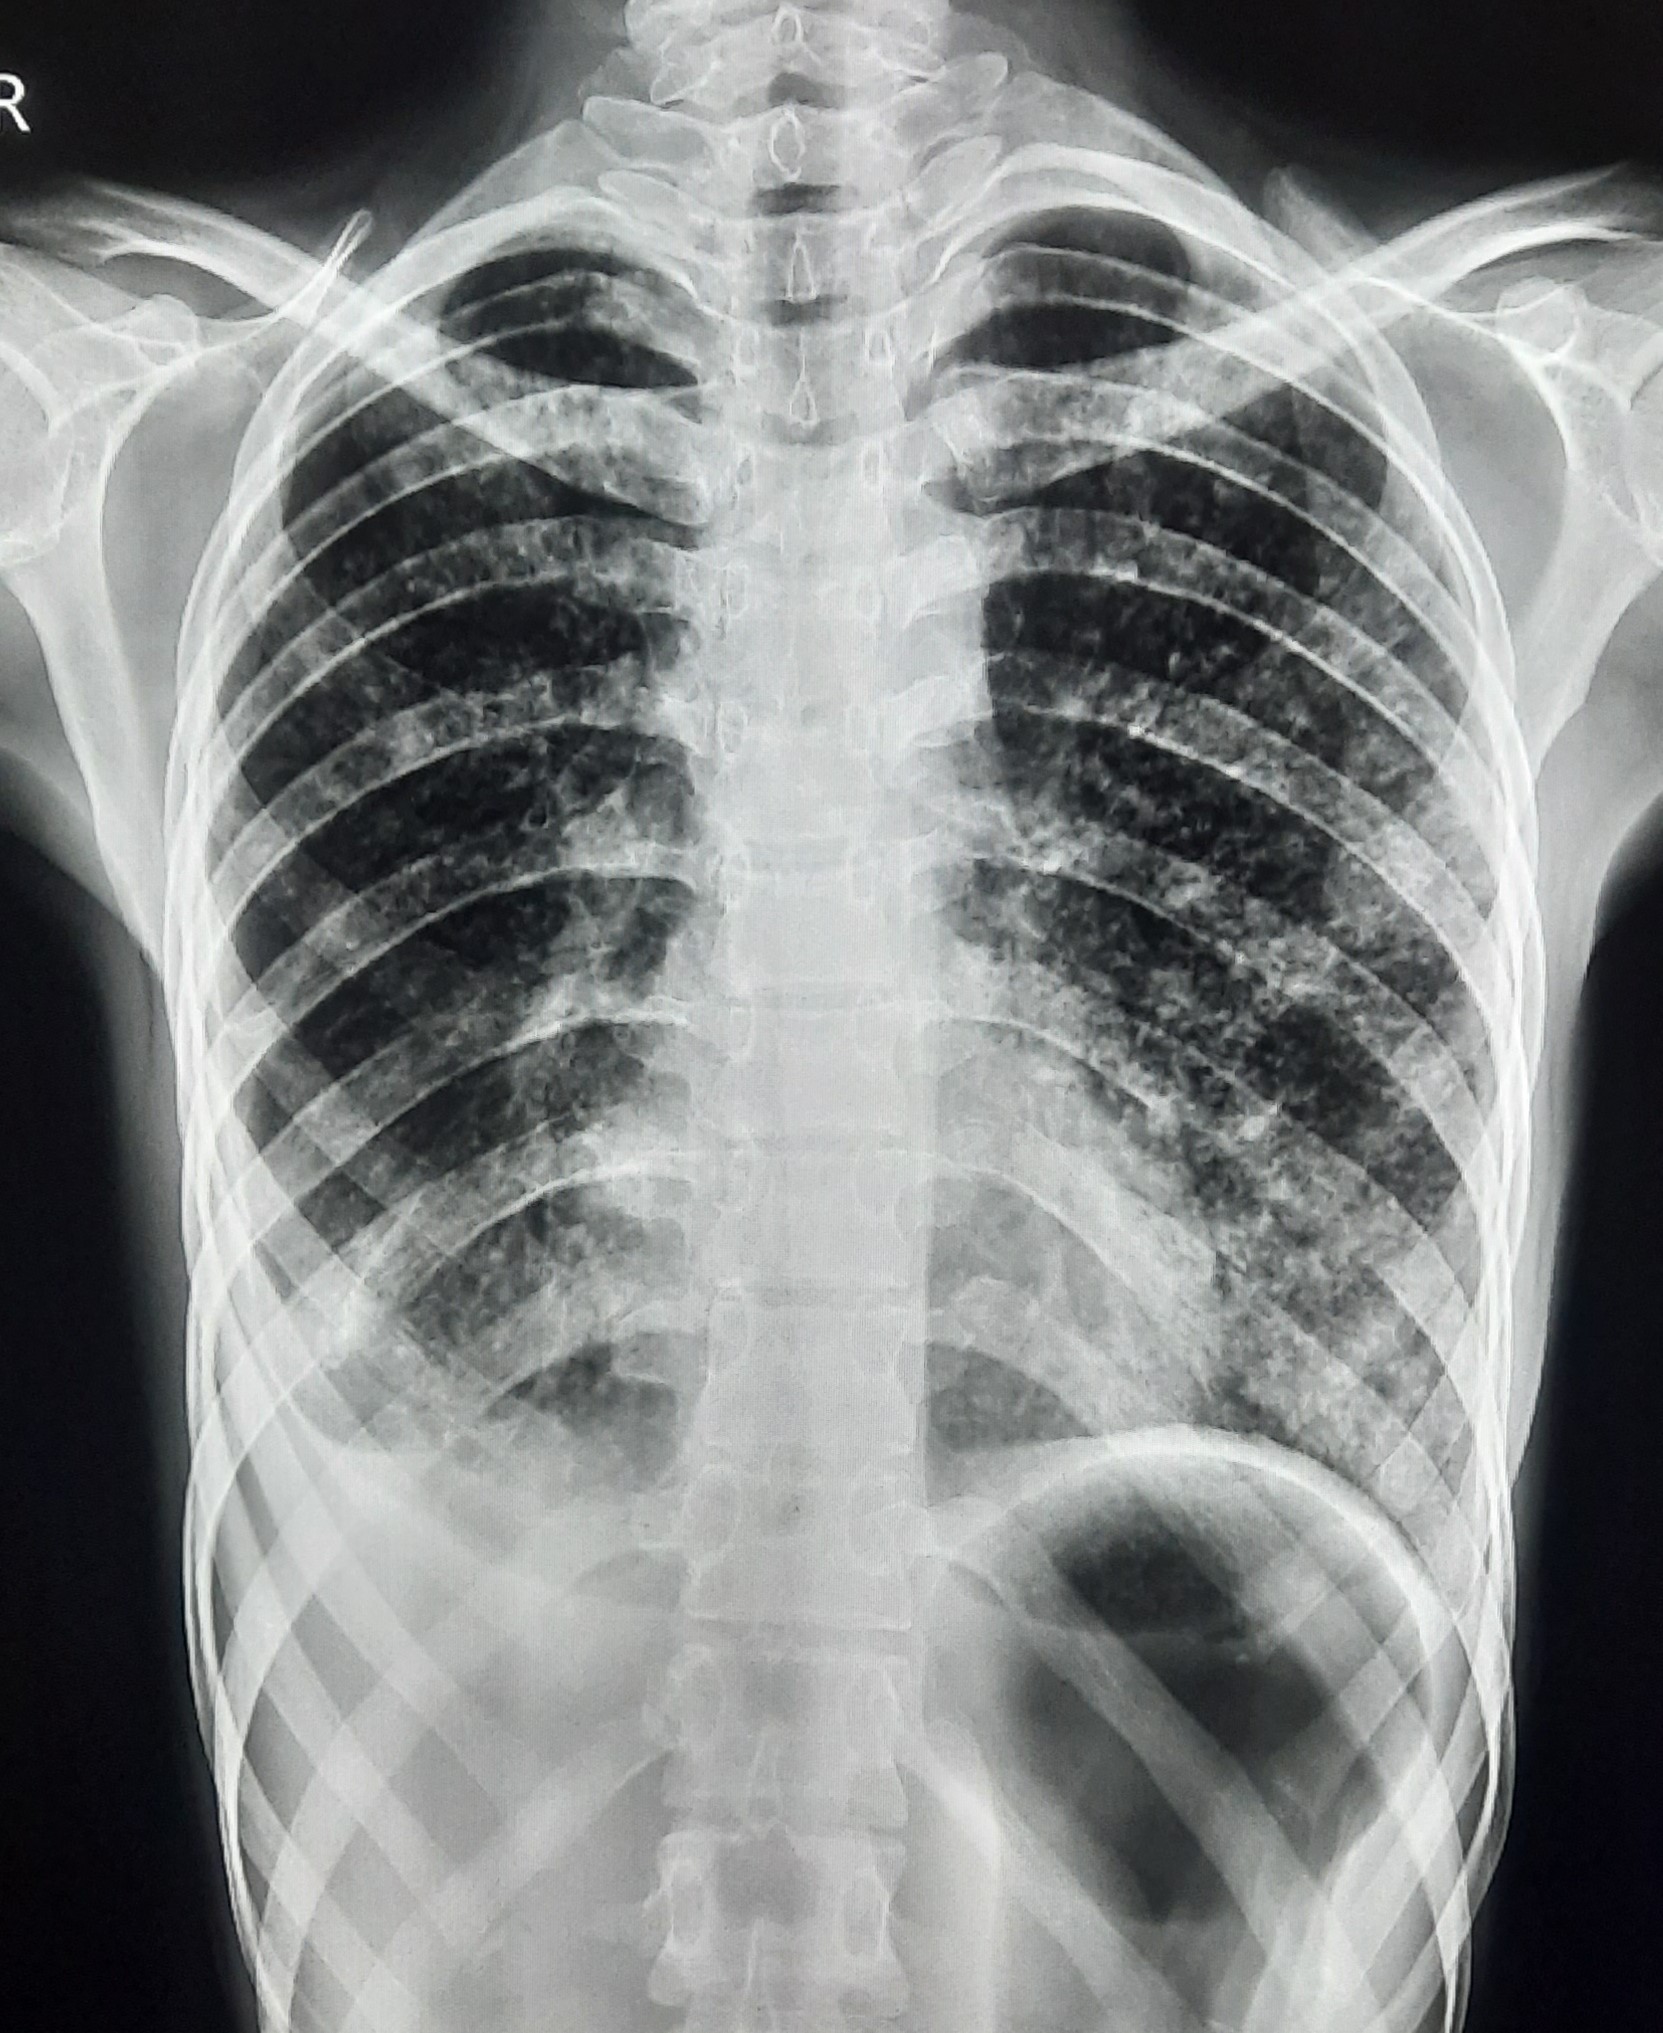

| 103 | IGGMC, Nagpur, Nagpur | P2 | 29-4369 | Vandana Kumbhare | Consent taken on Paper | 30 Yrs. |

Provisional Diag : Relapse PTB ?

Final Diag : Post TB sequalae |

Post TB Sequelae | Right Sided Fibro cavitary Changes Present, Right Pleural Thickening Present, Left Middle Zone linear opacity Heald Fibrotic Band ? | Abnormality visible on x-ray |